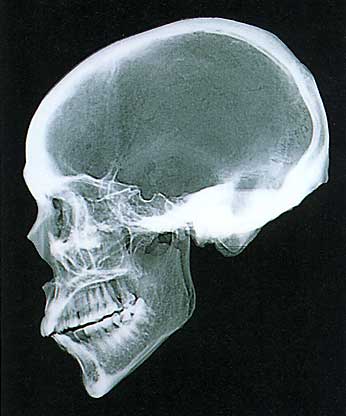

江戸時代人男性

(標本・国立科学博物館/撮影・神奈川歯科大学放射線科)